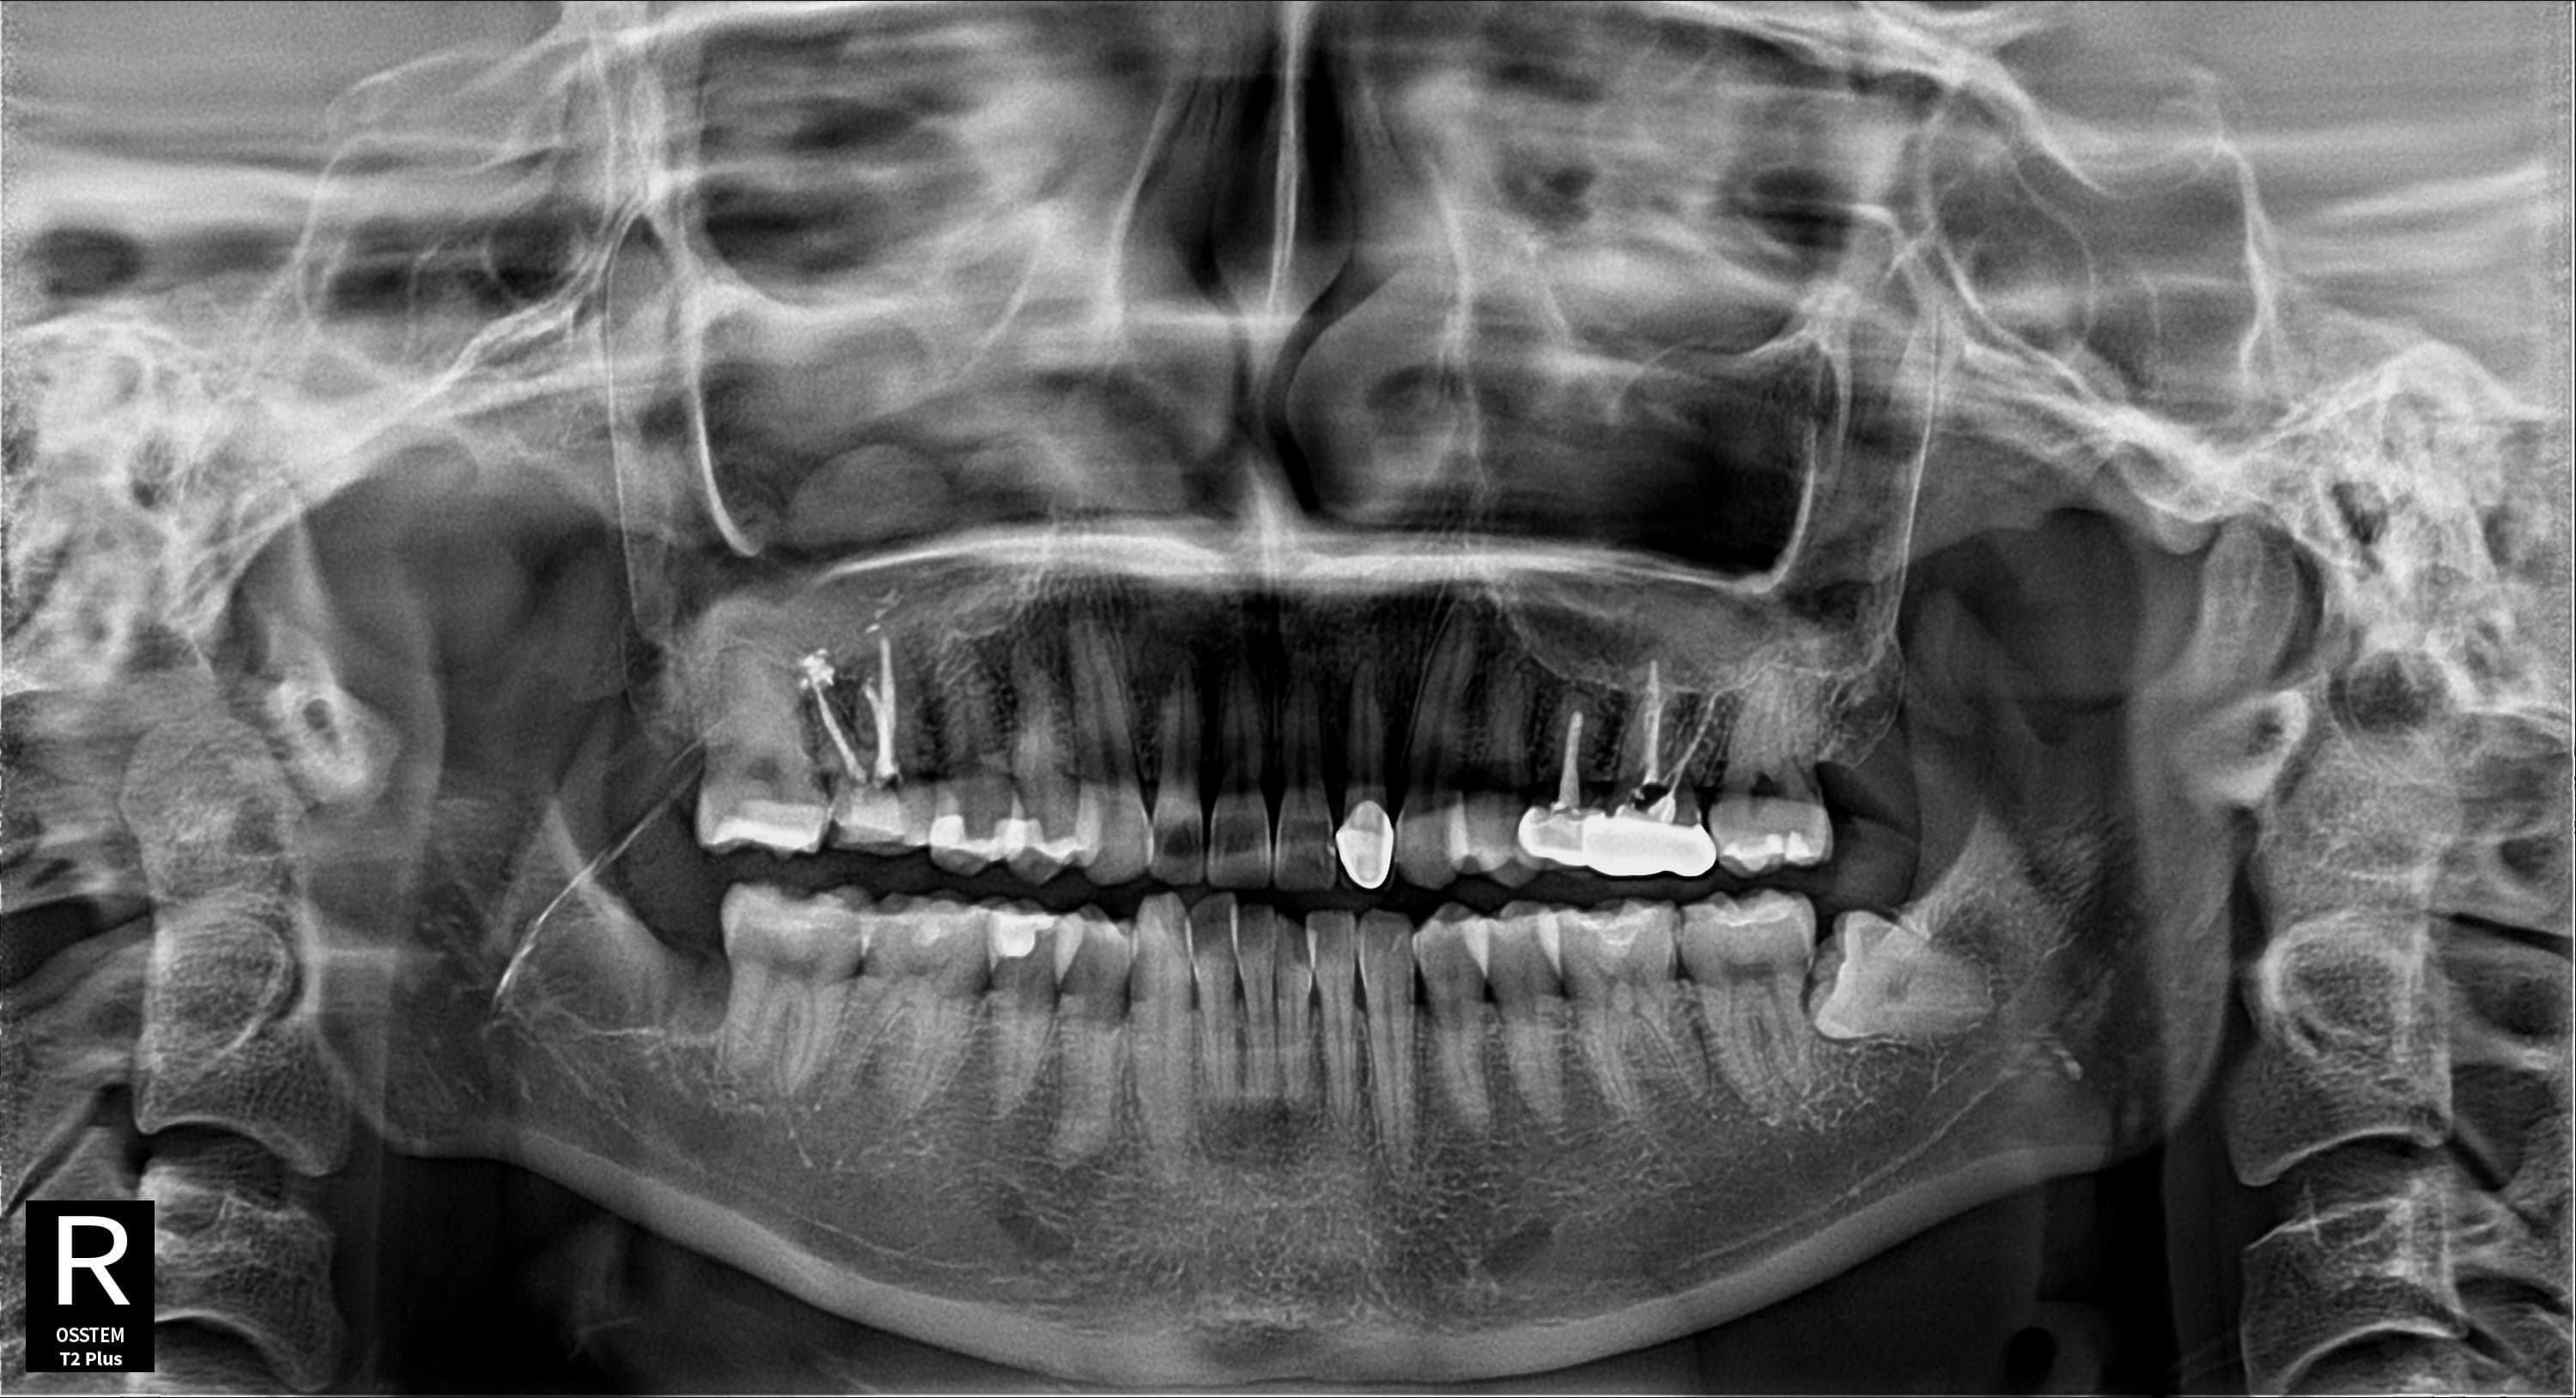

임플란트 + 사랑니 동시 시술

임플란트 식립과 사랑니 발치를 한번에

Before

After

임플란트 식립과 사랑니 발치를 동시에 진행하여 내원 횟수 최소화